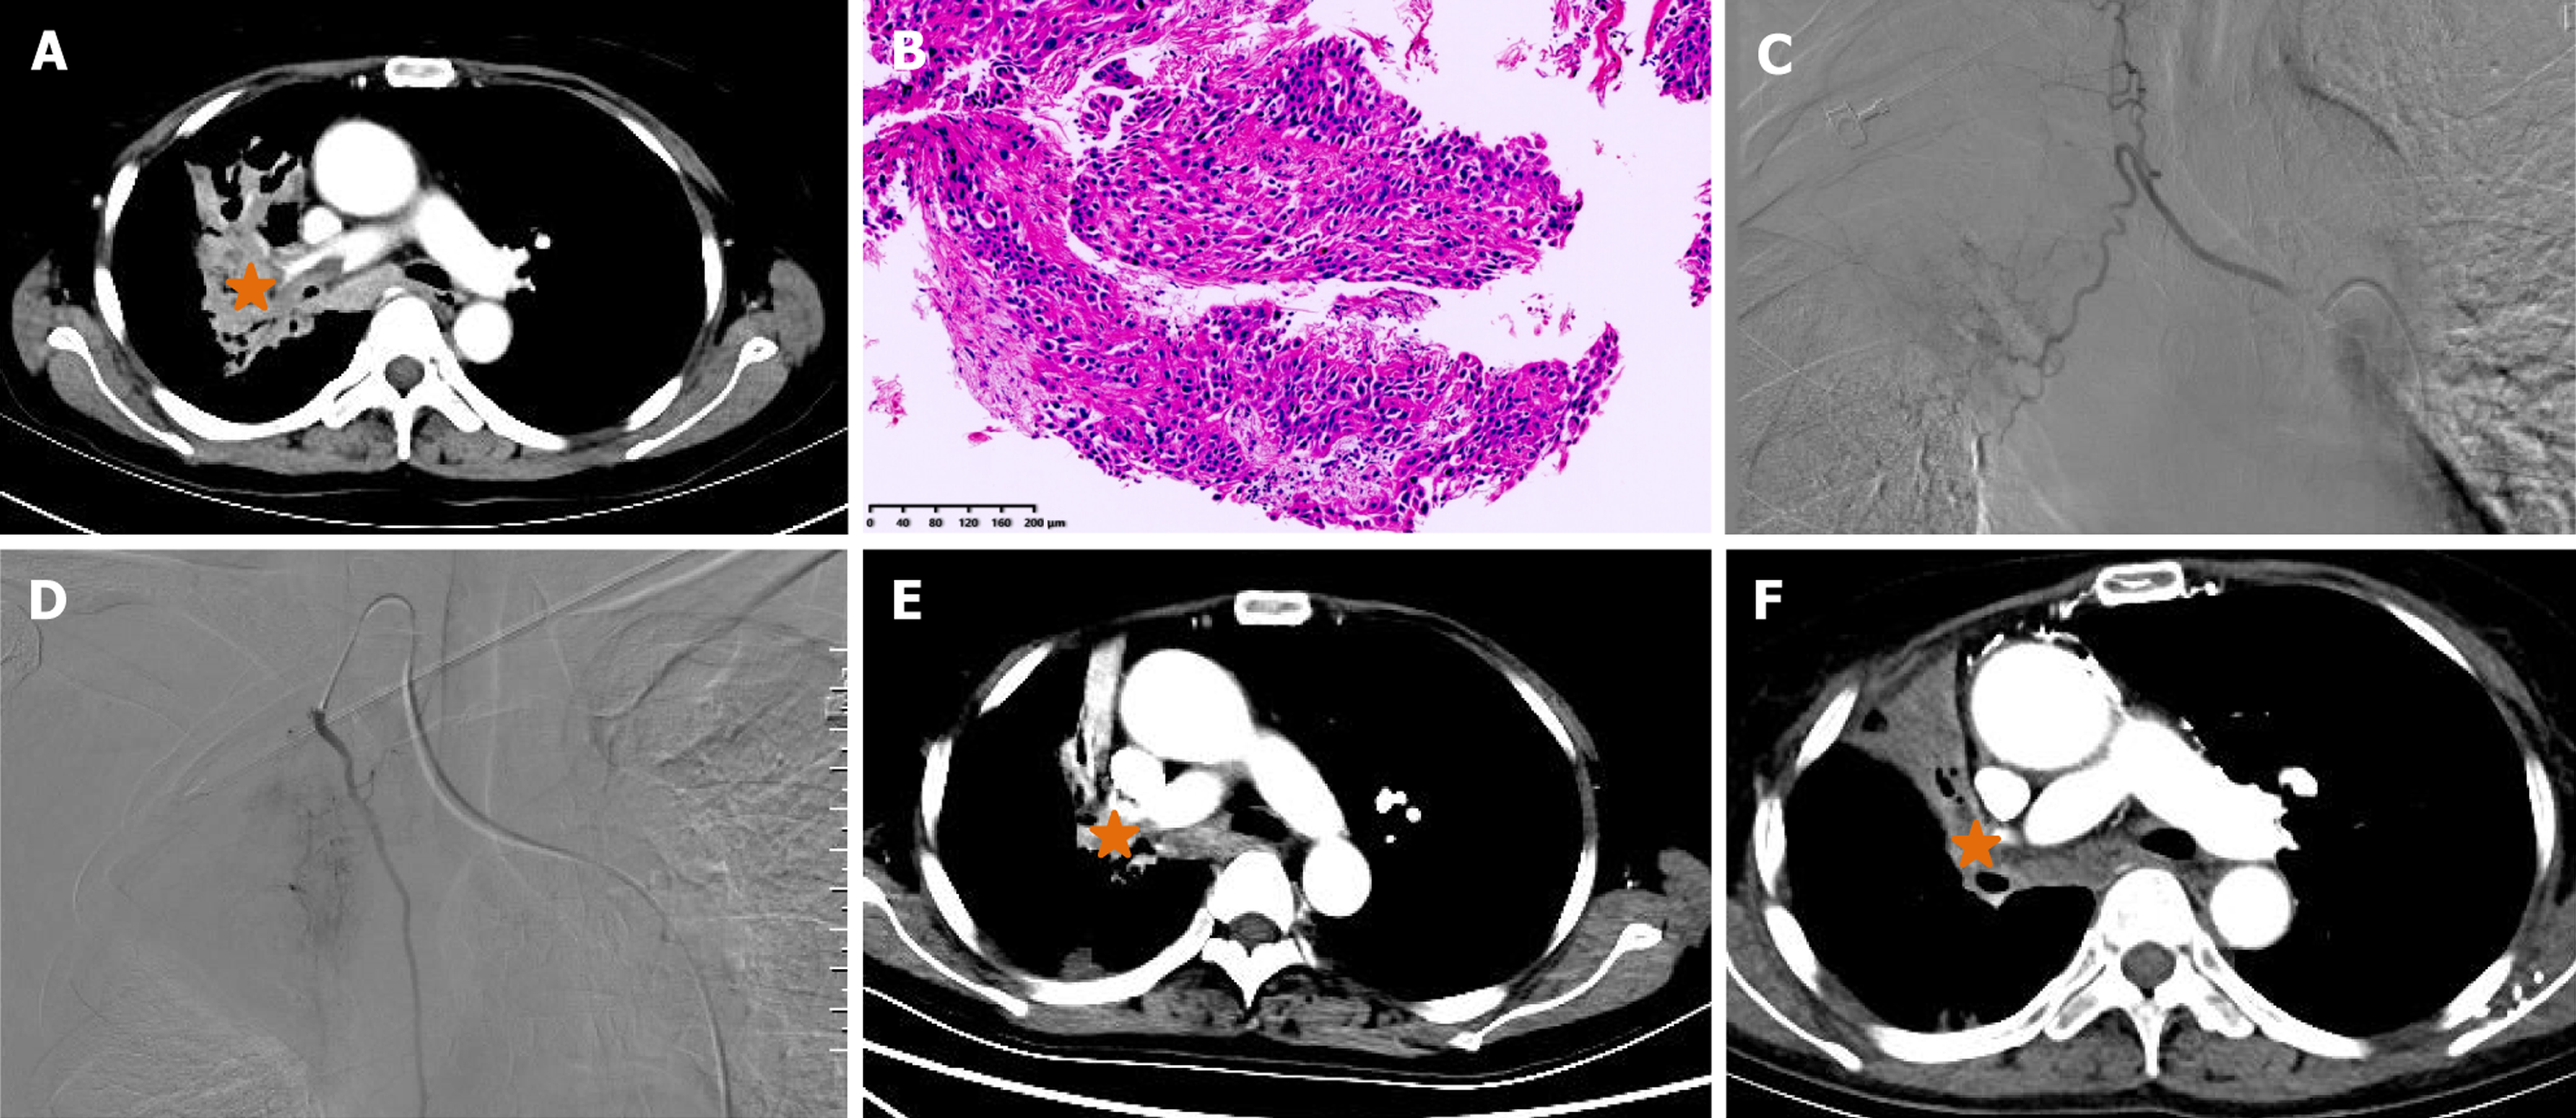

This retrospective study was approved by the Institutional Review Board of Zhengzhou university committee on human investigation, with all methods conducted in compliance with the relevant guidelines and regulations. As this study was designed as a retrospective study with clinical data analysed retrospectively and anonymously, the need for informed consent was waived by the Institutional Review Board of the First Affiliated Hospital of Zhengzhou University (No. 2023-KY-1002-002). All records were de-identified and stored in encrypted computer after data collection. A total of 123 patients with unresectable NSCLC who were treated in our department from July 2016 to July 2023 were retrospectively analysed. The inclusion criteria: (1) Biopsy proven NSCLC; (2) TNM stage II-IV according to the American Joint Committee on Cancer (AJCC) 7th Edition Cancer Staging System (Figures 1A, 2A, 2B, 3A and 3B); (3) Unresectable NSCLC or refused surgical resection due to severe comorbidities, advanced age and financial difficulties; and (4) Age 18 years to 85 years. The exclusion criteria: (1) Child-Pugh stage C or D; (2) Severe lung or heart dysfunction; (3) Severe infection; (4) Lactation or pregnancy; (5) Allergic to chemotherapeutic drugs or contrast agent; (6) Eastern Cooperative Oncology Group (ECOG) score > 2; (7) White blood cell < 3000 cells/mm3; (8) Total bilirubin > 2 mg/dL; and (9) Creatinine > 2 mg/dL.

DOX, OXA or GEM was loaded using CalliSpheres beads (Jiangsu Hengrui Medicine Co. Ltd., Jiangsu Province, China) for 30 minutes, and then mixed with iodixanol contrast developer in a 1:1 ratio before embolisation. DEB-TACE was performed under fluoroscopic guidance. After successfully puncturing the femoral artery, a 5-F sheath was inserted, and a 5-F Cobra catheter (Terumo, Japan) was inserted into the bronchial artery, intercostal artery or internal thoracic artery for angiography to identify the location of the tumour-feeding artery[14]. Next, a 2.6-F microcatheter (Asahi, Japan) was inserted into these arteries for advanced superselective catheterization. Chemotherapeutic drugs were infused into the tumour mass via the microcatheter. The total dosage of the chemotherapeutic agent was allocated according to the extent of tumour staining observed in each artery if there were three or more feeding arteries feeding the tumour[15]. Then, 1 g of drug-eluting CalliSpheres beads was used for chemoembolisation until blood flow stopped (Figures 1B, 1C, 2C, 3C and 3D).

All patients were followed up until the study endpoint or death. At approximately 1-, 3- and 6-month follow-up after treatment initiation, the treatment response was evaluated via chest CT according to the response evaluation criteria in solid tumors 1.1 criteria[16] (Figures 1D-F, 2D, 3E and 3F). Progression-free survival (PFS) was defined as the time interval from DEB-TACE treatment to disease progression or death, whichever occurred first. Overall survival (OS) was defined as the time interval from the DEB-TACE treatment to death. Objective response rate (ORR) was defined as the sum of complete response and partial response, and disease control rate (DCR) was calculated as the sum of complete response, partial response and stable disease. Adverse events were monitored and graded according to the National Cancer Institute Common Toxicity Criteria for Adverse Events version 4.03[17].